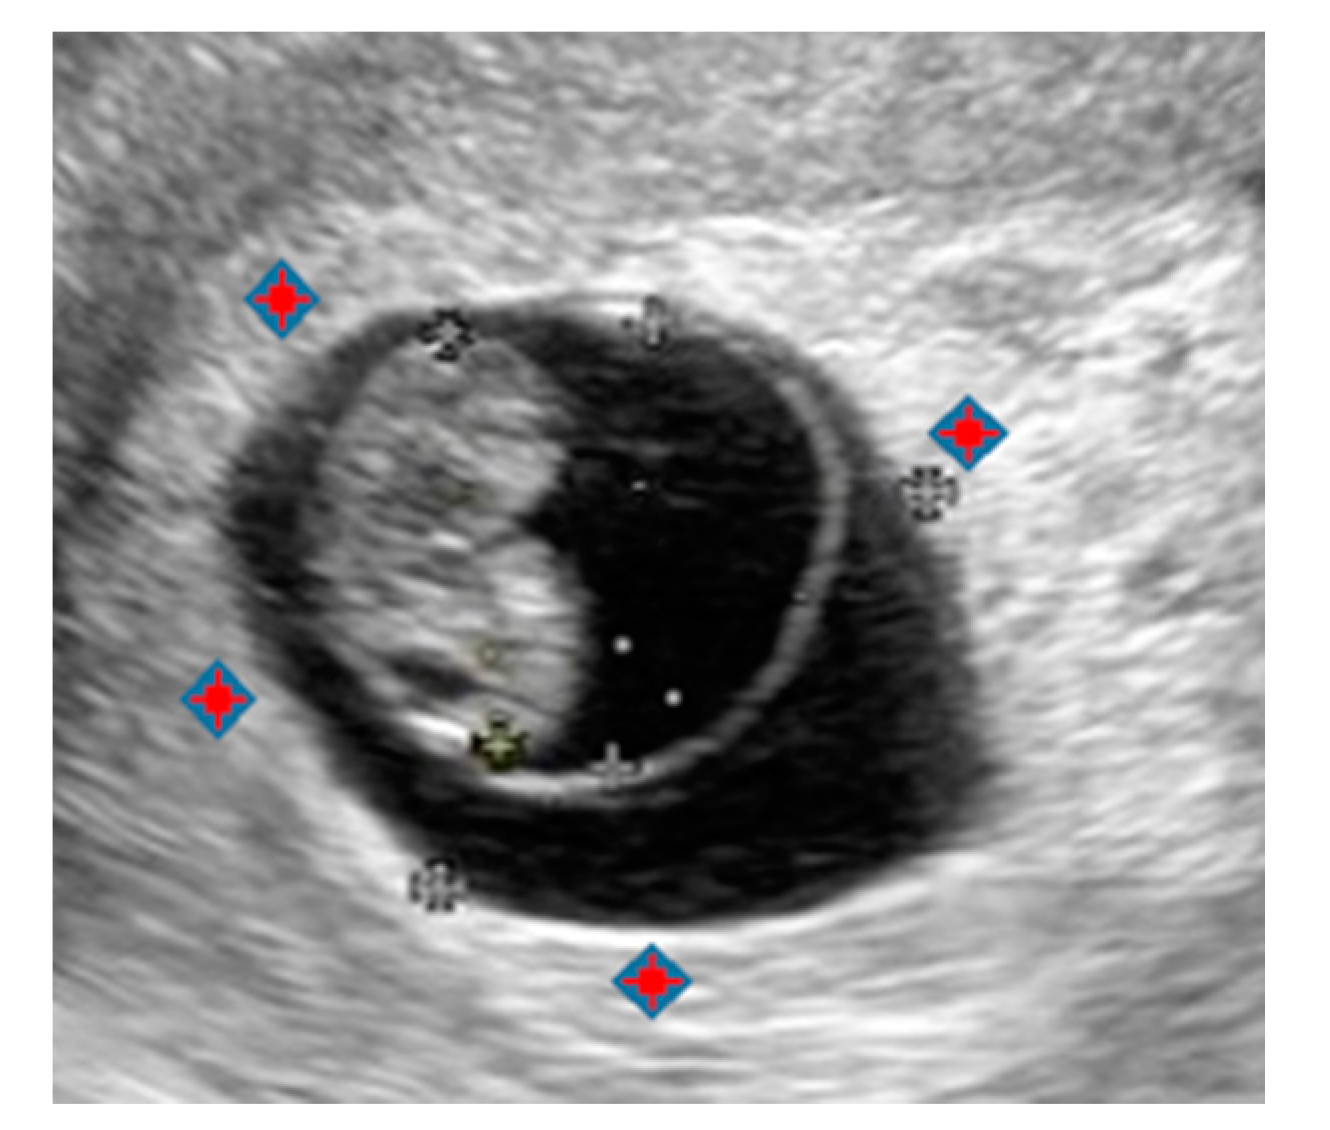

Figure 3. Ultrasonographic image at 7 w 3 d (19.3 × 13.8 mm). The red marks show the lacunar space where AE is injected.

The lacunar space occupies the hyperechoic ring (decidua capsularis) created around the GS by chorionic response [17,18]. In the CV-T therapy, 100% pure AE (Anhydrous Ethanol Injection; Pfizer, Tokyo, Japan) was injected into the lacunar space, rather than in the GS, under high-intensity imaging TVU guidance, using a 23-G Cathelin needle (Kitazato Medical, Tokyo, Japan).

Since 1 mL of AE was injected into the tissues over 30 to 40 pushes (0.025–0.03 mL per push), AE did not enter directly into the vein, and thus did not circulate in the systemic blood flow. Occasionally, the white ring was not visible clearly. In such cases, transvaginal ultrasound Doppler image was used to detect the presence of blood flow where the white ring should have been, and AE was injected into the site. The cases in which the white ring was not clearly visible tended to require multiple treatments owing to uncertainty regarding the exact site of injection.

The lacunar space cannot be observed directly; however, it is present in the decidua capsularis, thickened by the chorionic reaction around GS, and appears as a hyperechoic inner ring (white echogenic rim or “white ring”) on TVU (Figure 4) [18,19]. Figure 6 shows a photograph of the chorionic sac containing a fetus spontaneously aborted at 7 w 5 d. The chorionic villi regress and disappear, resulting in a smooth chorion (recognized from the 3 o’clock to 6 o’clock direction), or they persist and form a villous chorion (recognized from the 6 o’clock to 3 o’clock direction) to form a fetal component of the placenta.